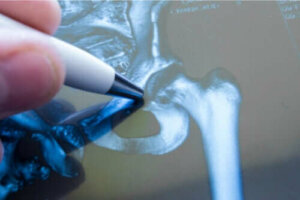

Na een ernstige val is dringende medische hulp essentieel, vooral als de patiënt op leeftijd is. De arts zal een noodröntgenfoto maken, die de omvang van de breuk zal laten zien. Afhankelijk van de ernst van het letsel zal de arts beslissen welke ingrepen hij zal uitvoeren.